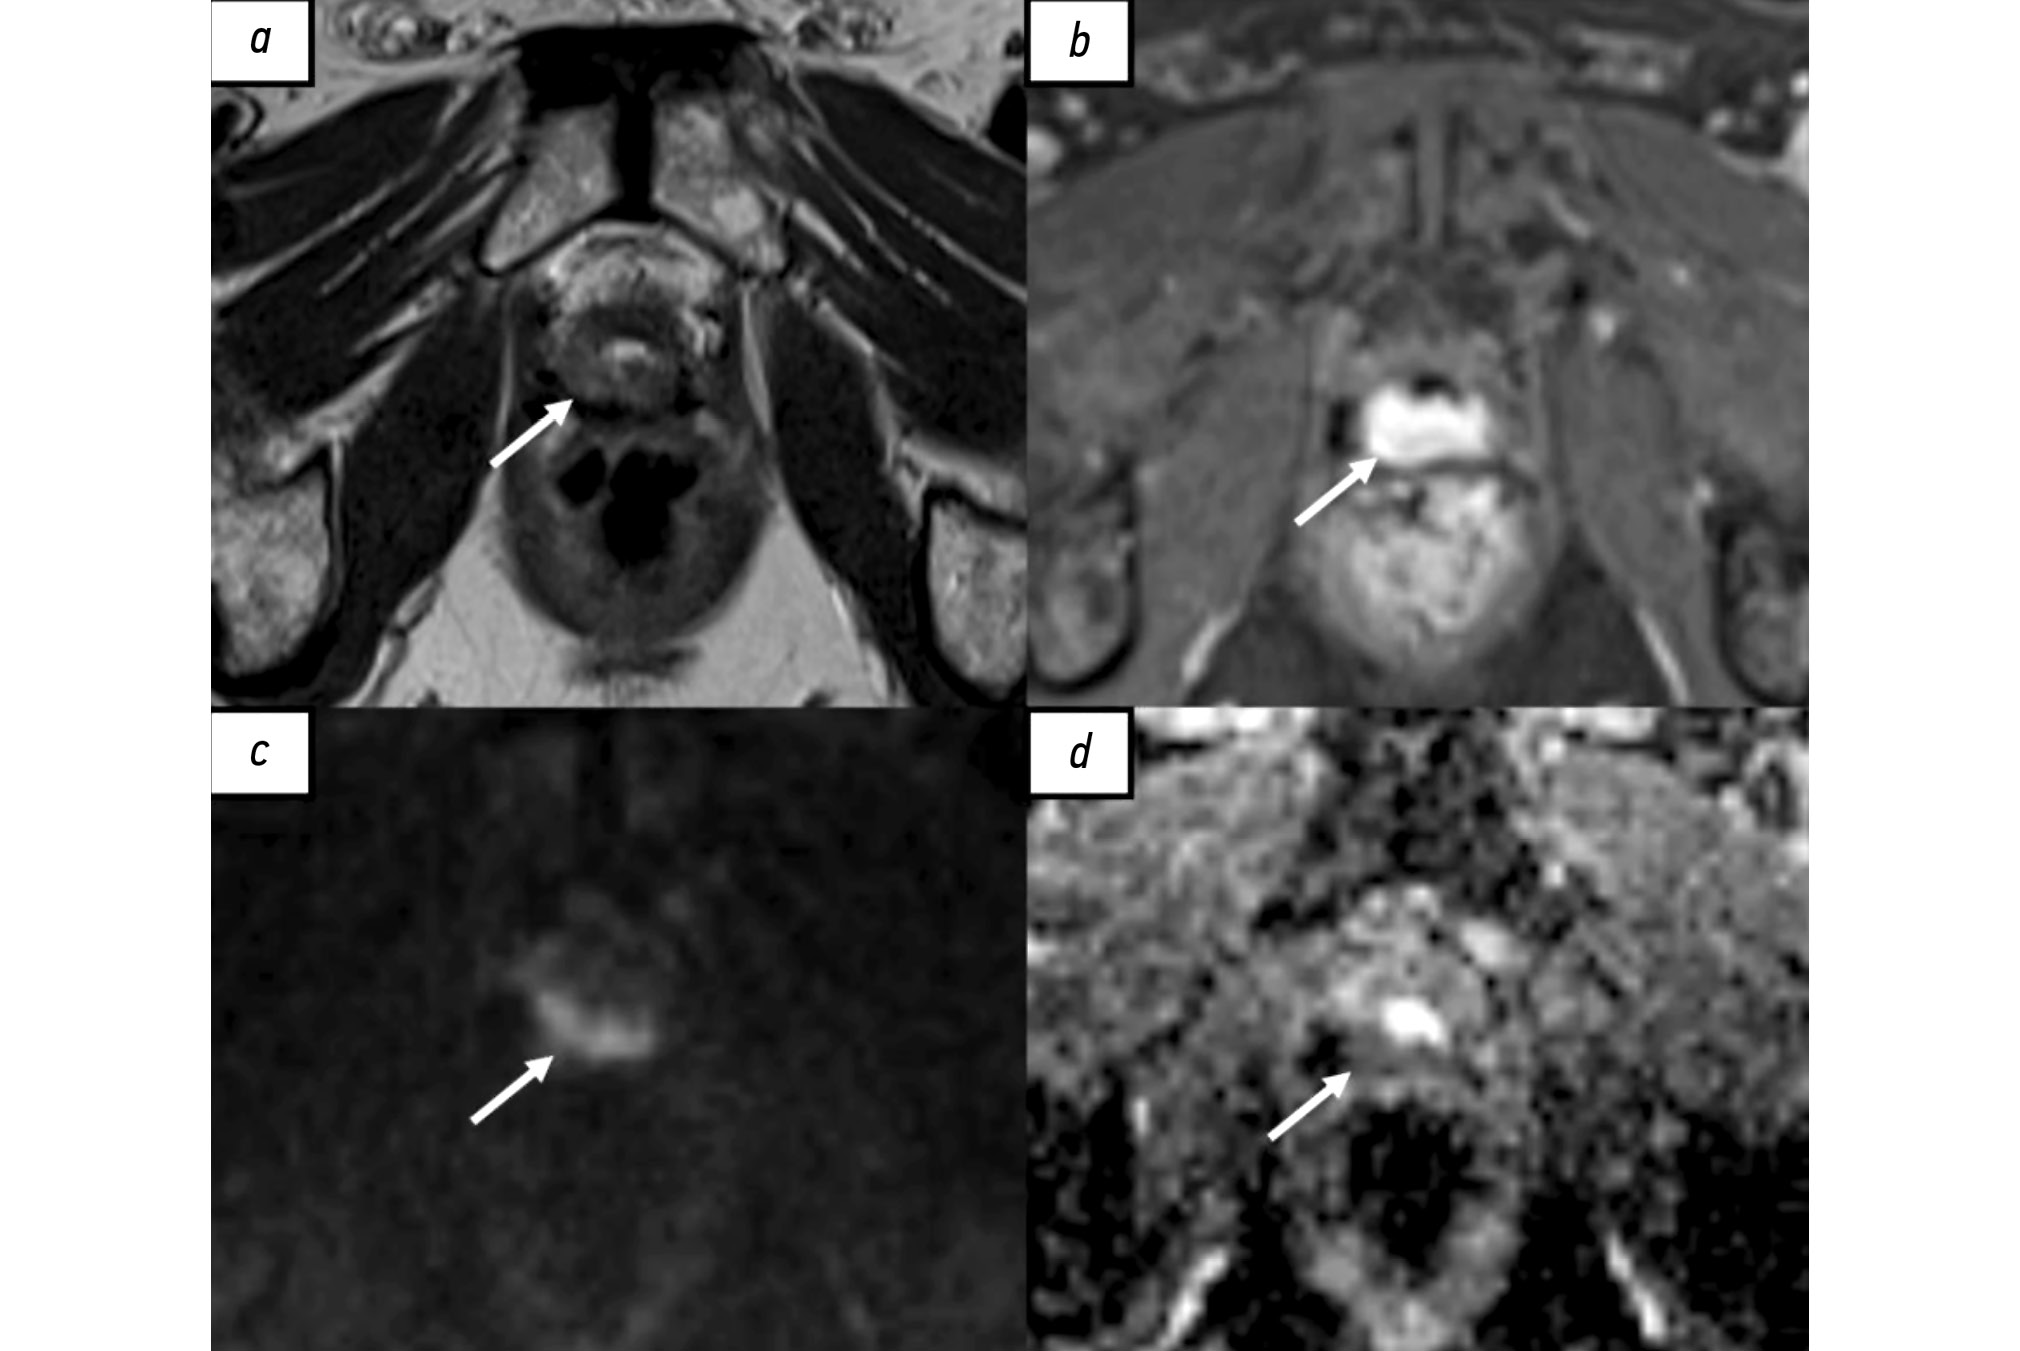

- Kwon T, Kim JK, Lee C, et al. Discrimination of local recurrence after radical prostatectomy: value of diffusion-weighted magnetic resonance imaging. Prostate Int. 2018;6(1):12–17. doi: 10.1016/j.prnil.2017.05.002 EDN: YCZHET

- Panebianco V, Barchetti F, Sciarra A, et al. Prostate cancer recurrence after radical prostatectomy: the role of 3-T diffusion imaging in multi-parametric magnetic resonance imaging. Eur Radiol. 2013;23(6):1745–1752. doi: 10.1007/s00330-013-2768-3 EDN: WABISI